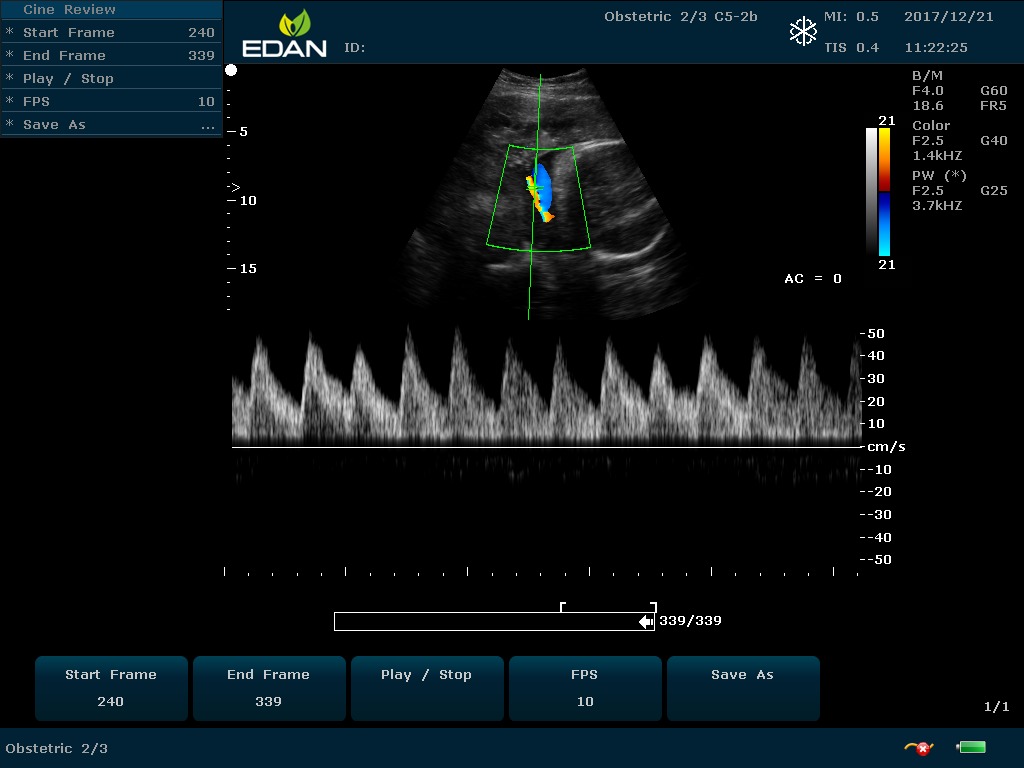

Особенность U60 Edan — расширенное применение. Ультразвуковой аппарат рекомендован для абдоминальных исследований, гинекологии и акушерства, кардиологии, педиатрии, урологии, изучения малых органов, сосудов. Для U60 Edan используются конвексные, линейные, фазированные и внутриполостные датчики.

Передовые технологии позволяют повысить качество визуализации в несколько раз. УЗИ-аппарат U60 Edan отличается возможностью быстрой настройки визуализации. Специальные функции позволяют моментально отображать данные за счет быстрой оптимизации параметров. Режимы визуализации: B-mode, M-mode, Color Doppler, Power Doppler Imaging, Pulsed Wave Doppler, Continuous Doppler.

• Импульсная Допплерография

• Непрерывноволновая Допплерография

• Спектральный Допплер с высокой частотой повторения импульсов